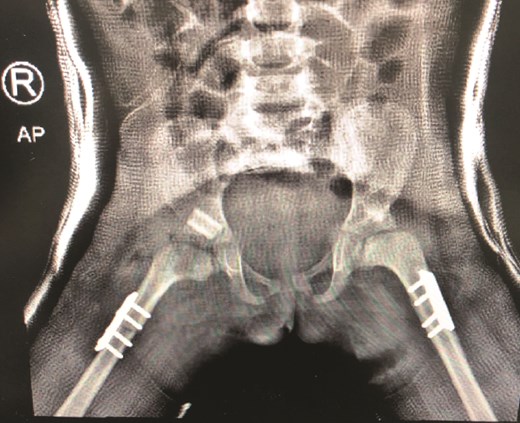

The patient underwent left hip open reduction, pelvic osteotomy, femoral shortening and hip spica followed by open reduction, pelvic osteotomy, femoral shortening and hip spica for the contralateral side six months later (Figs 2–4), the intervention was similar to regular DDH cases, no differences were noted during the surgical management. The patient was followed up closely in the clinic, and she had the implants removed after one year (Fig. 5). The patient recovered fully without any apparent postoperative complications. She was followed up in the clinic for 3 years, and she recovered fully without any complications.

(a) Post spica application lateral view. (b) Post spica application AP view.